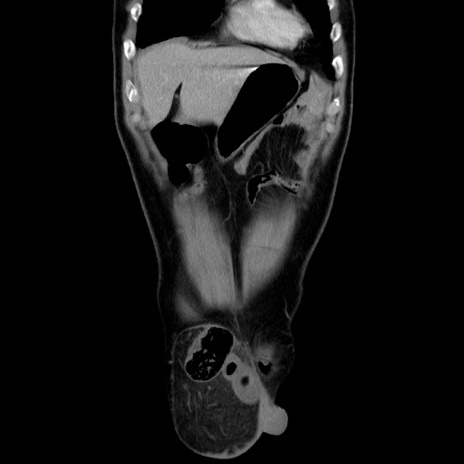

矢状断像

【症例】60歳代 男性

【主訴】右鼠径部膨隆

【現病歴】1年程前より右鼠径部膨隆あり。自己にて還納可能だったため放置していた。3時間前より右鼠径部の脱出を認め、還納困難となり受診。

【既往歴】高血圧

【身体所見】右鼠径部に小児頭大の膨隆あり。弾性硬であり、用手還納は困難。左鼠径部にも膨隆を認める。脱出はなし。